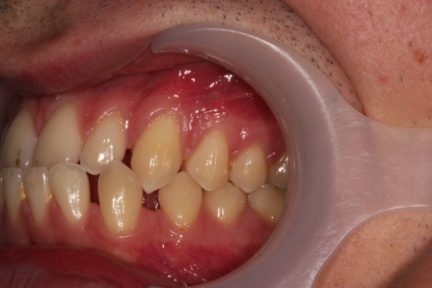

Élastiques : Classe III, nivellement de la courbe de Spee, ingression, expansion, rétraction, réduction interproximale

- Nous avons conçu ce traitement avec un changement hebdomadaire des aligners

- Nous avons commencé par élargir l'arcade supérieure et perdre du couple sur les incisives inférieures

- Après 19 aligners, nous avons effectué une réduction interproximale sur l'arcade inférieure et utilisé l'effet de chaîne en C pour fermer tous les espaces

État final